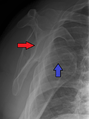

- An anterior dislocation of the shoulder

Anterior dislocation of the right shoulder. AP X ray